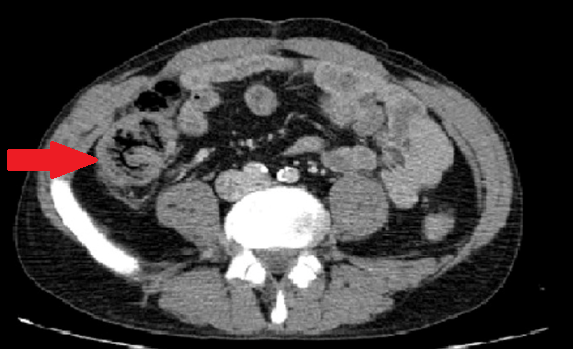

CT κοιλίας. Κόκκινο βέλος — Τυφλίτιδα. Σημαντική πάχυνση τοιχώματος τυφλού (Ευγενική παραχώρηση Dr. V. Penopoulos)